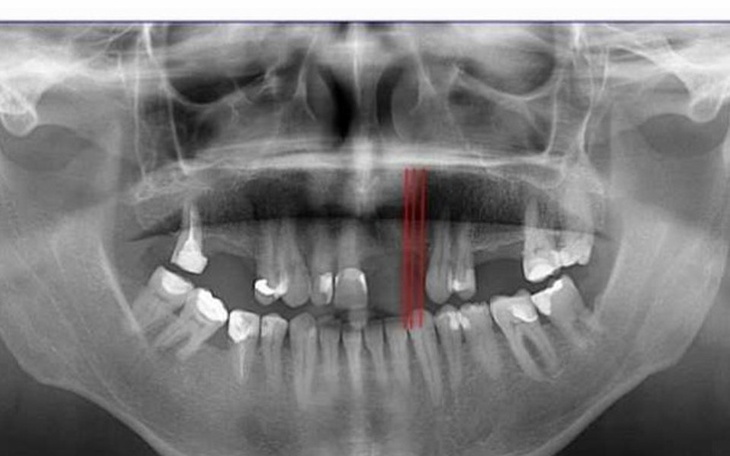

Witam mam 21 lat moją pasją jest sport , od urodzenia żyję z wadą wrodzoną rozszczepem wargi obustronnej i nosa ,jestem po 6 operacjach plastyczno-chirurgicznych miedzy innymi wszczepiania kości z biodra do wyrostka zębodołowego i operacjach wargi i podniebienia ,zbieram pieniądze na operacje wszczepu kości i przesunięcia kości szczęki do przodu a kości żuchwy do tyłu oraz na leczenie ortodontyczne, koszt tych operacji i leczenia to kilkadziesiąt tysięcy złotych ,bardzo proszę o wsparcie, zapewniam że każda złotówka pójdzie tylko i wyłącznie na operacje i leczenie, wszystkim osobom które pomogą z góry serdecznie Dziękuję!!!